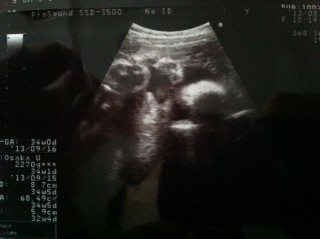

写真:34w0d:ちぃさん:1790g

34wぴったりの横顔のエコー写真です。 大きさは平均より小さめで1790g。周りの人達が2000gを超えてきている中、うちはマイペースな小さめベビーみたいです! でも、胎動は痛いくらいに激しめなので気にしないです\(^o^)/